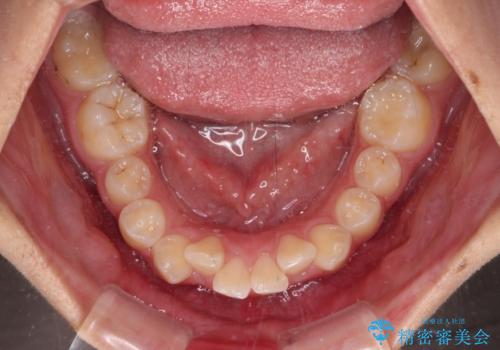

- 下唇の上に乗っかってしまうくらい前歯が飛び出していることを気にして来院された患者様です。

唇を閉じようとするとオトガイ部に力が入ってしまい、うまく閉じることができない状態であったため、上下左右の第一小臼歯4本を抜歯して、ワイヤー装置にて矯正治療を行うこととしました。

飛び出した前歯はしっかりと引っ込み、横顔の印象が大きく変化しました。